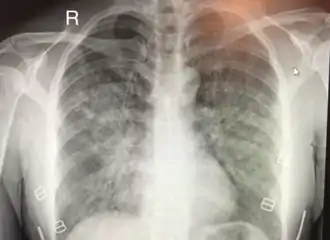

L'œdème pulmonaire de haute altitude (OPHA) est une forme mortelle d'œdème pulmonaire (accumulation de liquide dans les poumons) non cardiogénique qui se produit chez les personnes en bonne santé à des altitudes généralement supérieures à 2 500 mètres[1]. Cependant, des cas ont également été signalés entre 1 500 et 2 500 mètres chez des sujets plus vulnérables.

Le consensus de Lake Louise pour l'œdème pulmonaire en haute altitude a défini des critères largement utilisés pour définir les symptômes de l'OPHA[5]. Après un récent gain d'altitude, la présence de :

- au moins deux symptômes parmi :

- essoufflement au repos,

- toux,

- faiblesse ou diminution de la performance physique,

- oppression thoracique ou congestion ;

- au moins deux signes parmi :

- craquements ou respiration sifflante (pendant la respiration) dans au moins un champ pulmonaire,

- coloration bleue de la peau (cyanose centrale),

- tachypnée (respiration rapide),

- tachycardie (fréquence cardiaque rapide),

- expectoration d'une mousse de couleur saumonée.